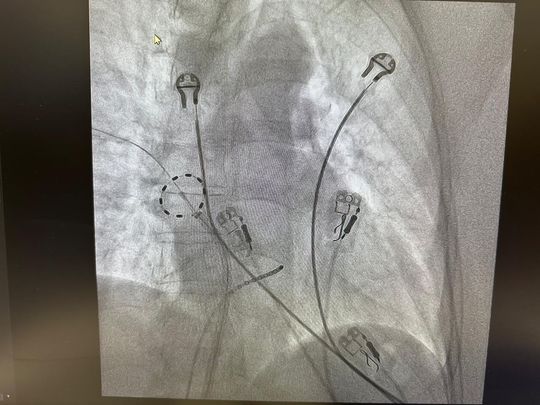

Ablacją w kraśnickiej 4Cardii

Zdjęcie: Ablacją w kraśnickiej 4Cardii